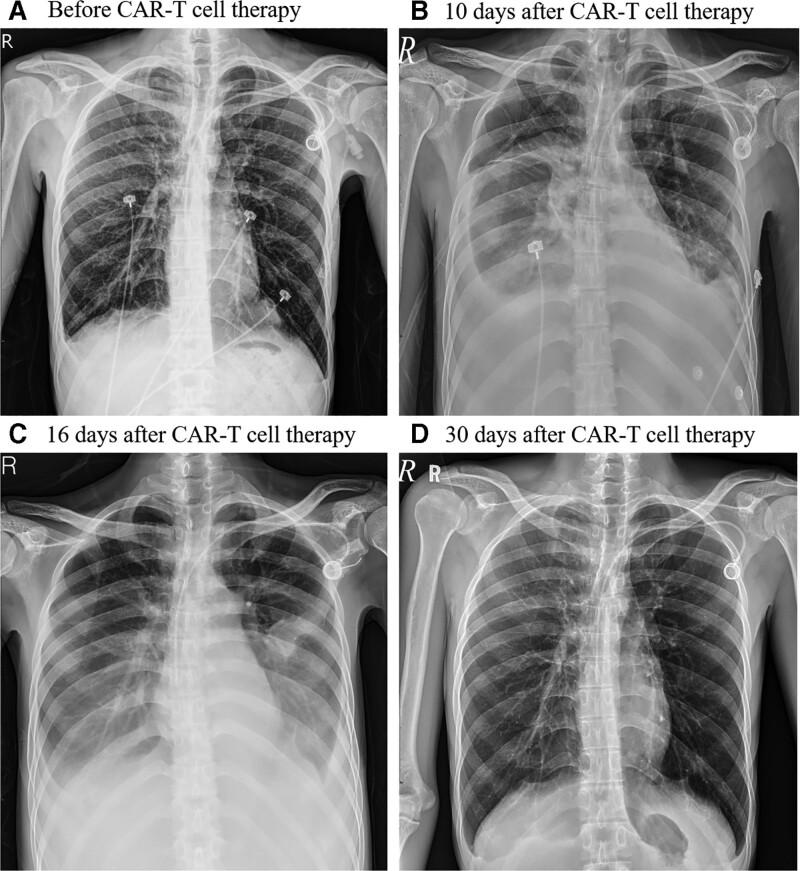

A 23-year-old male diagnosed with DLBCL relapsing after autologous peripheral blood stem cell transplantation was treated with anti-CD19-targeted CAR-T cell therapy. After CAR-T cell transfusion, he developed grade 3 CRS includes fever, dyspnea, tachycardia and hypotension. The symptoms of CRS persisted and chest plain film revealed bilateral pleural effusion.

一名 23 岁男性,在自体外周血造血干细胞移植后复发 DLBCL,接受了抗 CD19 靶向 CAR-T 细胞治疗。CAR-T 细胞输注后,他出现了 3 级 CRS,包括发热、呼吸困难、心动过速和低血压。CRS 症状持续存在,胸部平片显示双侧胸腔积液。

On 30-day follow-up, the patient was in stable clinical condition with complete remission of DLBCL on whole-body positron emission tomography scan.

30 天随访时,患者临床状况稳定,全身正电子发射断层扫描(PET)显示 DLBCL 完全缓解。